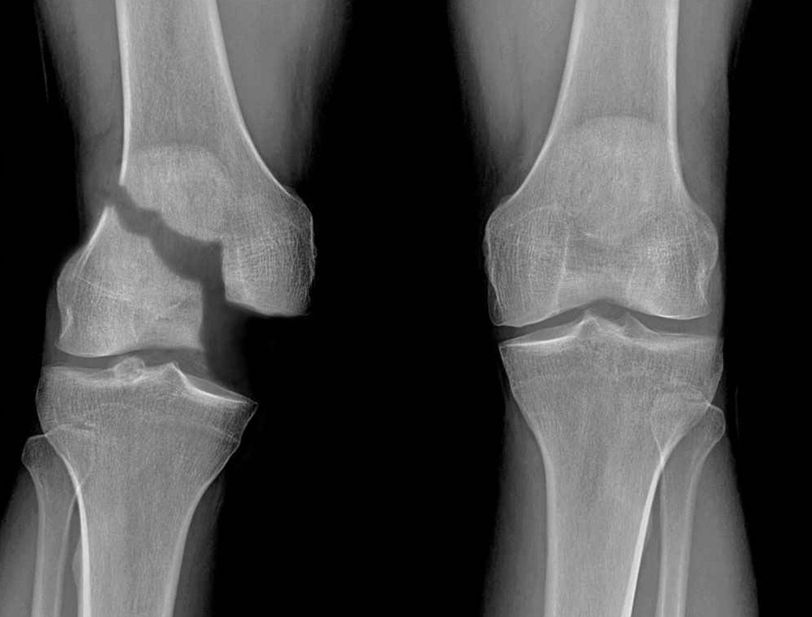

A Salter–Harris fracture or growth plate fracture is a fracture that involves the epiphyseal plate or growth plate of a bone. It is thus a form of child bone fracture. It is a common injury found in children, occurring in 15% of childhood long bone fractures.